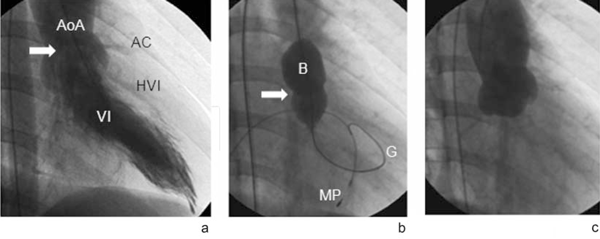

Caso 4: escolar de 10 años de edad, 23 kg, procedente de Tacuarembó, producto de tercera gesta, con antecedentes perinatales de madre portadora de diabetes insulinorrequiriente. Buen crecimiento y desarrollo. A los seis meses se detecta click y soplo sistólico en paciente asintomático, diagnosticándose EVAo, sobre válvula bicúspide, con electrocardiograma (ECG) basal normal (Figura 4a). A los 2 años de edad se describe hallazgo de frémito supraesternal A los 5 años refiere palpitaciones con el ejercicio, siendo la ergometría normal. Controles periódicos en policlínica de cardiología pediátrica. A los 9 años presenta dolor precordial al esfuerzo sin otra sintomatología acompañante. ECG: hipertrofia ventricular izquierda con sobrecarga diastólica. Ecocardiograma: estenosis valvular aórtica con gradiente de 70 mmHg, válvula engrosada, insuficiencia aórtica leve. Hipertrofia marcada del ventrículo izquierdo. Ergometría: descenso significativo del ST al máximo esfuerzo (Figura 4b). Se coordina y realiza estudio hemodinámico que mostró EVAo con válvula en domo y escasa motilidad, anillo de 25 mm y gradiente de 40 mmHg con severa hipertrofia ventricular izquierda. Se realizó valvuloplastia aórtica con catéter balón con un gradiente residual de 9 mmHg, sin insuficiencia aórtica residual (Figura 5). El control a los tres meses registró un ECG basal normal, gradiente valvular aórtico por ecocardiograma de 10 mmHg. Desaparición de las alteraciones de la repolarización ventricular en la ergometría (Figura 4c). Buena evolución.

Figura 5 a. Angiografia del ventrículo izquierdo (VI) en proyección oblicua anterior derecha. Se observa la válvula aórtica en domo con un estrecho pasaje sistólico central (flecha). Aorta ascendente (AoA). Hipertrofia ventricular izquierda (HVI) dada por el marcado aumento del espesor de la pared ventricular izquierda enmarcado entre la luz del VI y las arterias coronarias (AC). b. Proyección oblicua anterior derecha. Balon (B) posicionado en el anillo aórtico con la incisura correspondiente a la válvula aórtica estenótica (flecha). Cable de marcapaso en ventrículo derecho (MP). Guía de posicionamiento del balón en VI (G). c. Aortografía en proyección oblicua anterior derecha posvalvuloplastia demostrando la ausencia de insuficiencia valvular aórtica posprocedimiento.